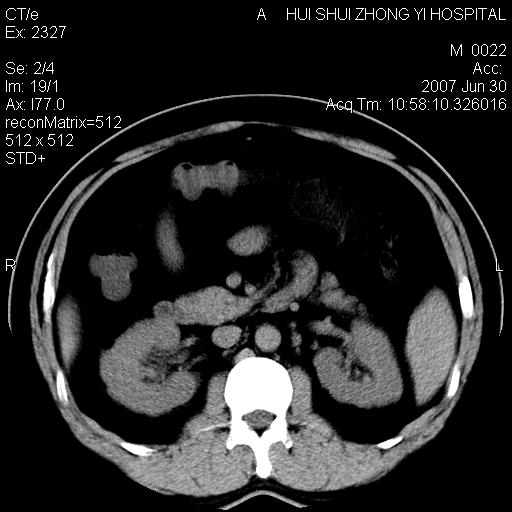

男,44岁,体检。

双肾结石

双侧肾盂、输尿管内结石,双侧肾脏轮廓呈波浪状,可能以前有过感染的

支持双肾结石

支持双肾结石,肝右叶低密度影为胆囊部分容积效应。

双肾结石.

肝右叶低密度影为胆囊部分容积效应?为什么s43.0层面下来不见胆囊影,而是相隔了一层才见胆囊影。这是按我们扫描的顺序发的,但是是追加扫描的。

双侧肾盂结石。

肝右叶低密度灶,增强!

支持双肾结石,肝右叶低密度影为胆囊部分容积效应

双肾结石,做个b超结合看一下。

病人呼吸动了,第四层应该在第五\\六层之间。肝右叶低密度影为胆囊部分容积效应。双肾结石。

双肾结石,少量腹腔水?

双肾结石,肝右叶低密度影为胆囊部分容积效应。

支持双肾结石,肝右叶低密度影为胆囊部分

支持双肾结石。与患人呼吸有关。布分容积效应。